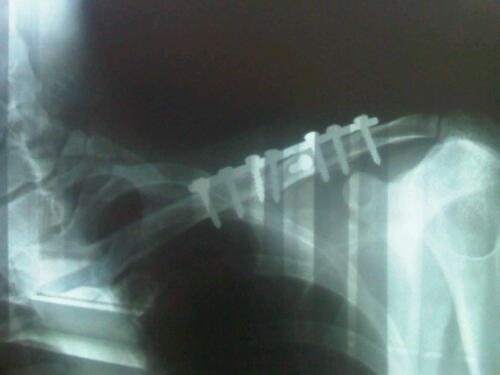

Biar lo tanpa busana di bandara, sensornya tetep aje bunyi cuit cuit ... tuh :ngakak mod.. minta cetak ama dudu mod.. :D dia punya enlarger :D . Bwahahaha ... kalo film 8x10 pake Kontak Print, di tempelin di kertasnya trus di sinarin. Yg namanya photo rontgen itu biar di cetak juga tetep kayak...